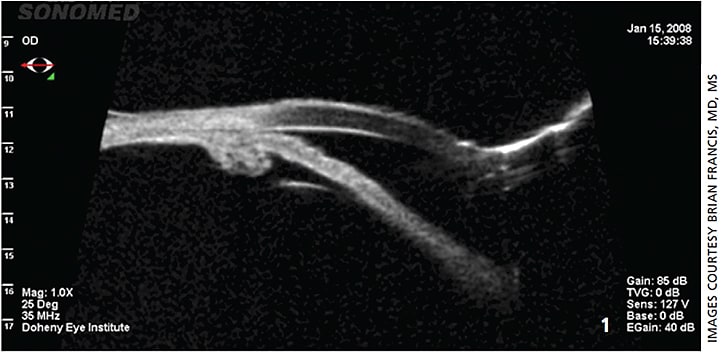

CASE 1: Figure 1. UBM image showing continued narrow angle approach with plateau iris conformation. Note the anterior placed ciliary processes that are prominent in both width and height.

A 58-year-old female presented with a history of intermittent angle closure. A peripheral laser iridotomy (LPI) was performed; however, postoperatively she had a persistent narrow angle and continued appositional angle closure.

Due in part to the negligible effect of the LPI, the diagnosis of plateau iris was made. She subsequently underwent cataract extraction with IOL implant combined with an endoscopic cycloplasty (ECPL). ECPL was selected in order to shrink her large and anteriorly rotated ciliary processes that were seen on UBM.

In this case, both UBM and endoscopic imaging were used. The UBM was the most important clinical imaging modality available due to its ability to not only image the insertion of the iris root but also the ciliary body. UBM also allowed for the viewing of the decreased size of the ciliary processes postoperatively. The 20-gauge endoscope (Beaver Visitec, Inc. and Endo Optiks) has the advantage of incorporating a camera, aiming beam and treatment laser into the same instrument. The combination of these three components allows for ECPL to be carried out through one incision. ECPL is beneficial in opening the angle in these severe plateau iris cases since it directly decreases the ciliary process width, thickness, area and the iris’ ciliary process contact length.1